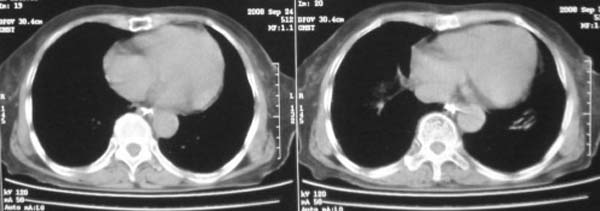

女,78岁,声嘶月余,否认有既往病史,有粉尘接触史10年。

颈部见多枚淋巴结肿大,考虑尘肺继发结核,喉部淋巴结钙化,不除外喉部慢性淋巴结炎、喉淀粉样变及类癌等

肺癌伴纵膈、双颈部淋巴结转移;尘肺。

右上肺癌伴肺内转移及纵隔淋巴转移 左上肺结核 图像有点模糊

考虑肺癌伴纵膈、双颈部淋巴结转移;

双上肺结节融合影,周围有纤维条索影,结合粉尘接触史,首先考虑尘肺。双侧颈部有增大淋巴结,有声嘶表现,肺癌淋巴结转移不能排除。可结合颈部淋巴结活检。